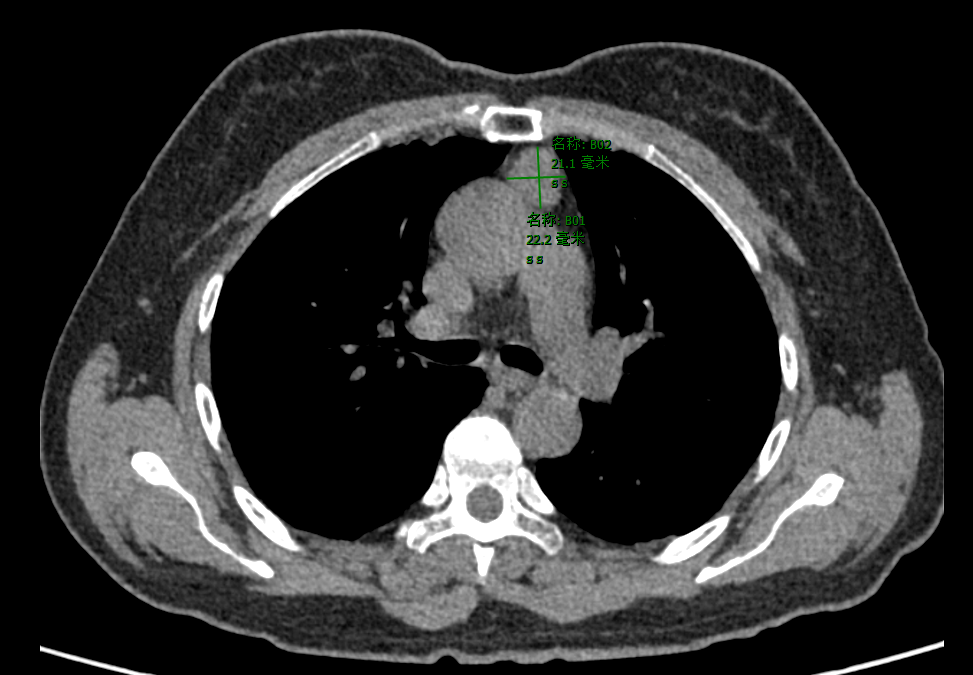

患者因胸部CT检查发现纵隔肿物,到广东医附院胸外科做进一步诊治。入院后进行了各项术前相关检查,患者心肺肝肾等功能良好,无高血压、糖尿病等基础病。纵隔肿物考虑胸腺瘤可能性大,经患者家属同意以及胸外科术前讨论后,胸外科医师团队选择达芬奇机器人辅助经剑突下入路切除纵隔肿物。

CT提示前纵隔占位